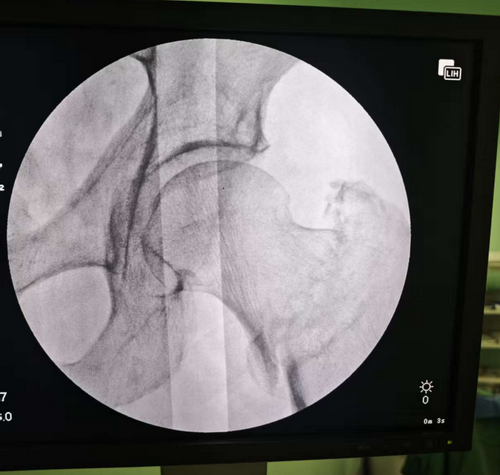

面对高龄与复杂病情,医院骨科团队没有轻言放弃。经麻醉科、心血管科、营养科、护理团队等多学科联合会诊评估,并与家属充分沟通后,决定为患者实施PFNA(防旋髓内钉)内固定术。手术在全麻下进行,借助C臂机精准引导,完成微创复位与固定,全程仅一小时,出血少,术后X光显示复位理想。本次手术突破“年龄即禁忌”的旧观念,通过术前营养支持、心功能优化、风险评估等系统准备,让96岁超高龄患者安全度过手术关,家属高兴地表示,爷爷术后状态非常好!